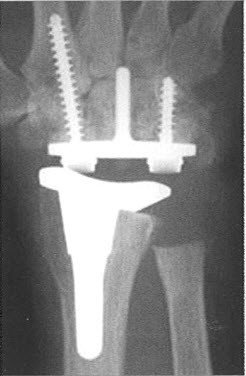

Bei zerstörtem Handgelenk kommt neben der Versteifung auch der bewegungserhaltende prothetische Ersatz des Handgelenks in Frage. Da der Funktionsverlust durch eine Handgelenkversteifung meist gut toleriert wird, kommen Kunstgelenkoperationen vor allem bei Patienten mit beidseitiger Handgelenkzerstörung in Frage. Die Belastbarkeit einer Handgelenkprothese ist beschränkt. Deshalb gelangt die Gelenkprothese vor allem in jenen Situationen zur Anwendung, in welchen der Erhalt der Beweglichkeit wichtiger ist als die Kraftentfaltung. Man muss sich jedoch bewusst sein, dass auch mit einer Handgelenkprothese keine normale Beweglichkeit des Handgelenks erzielt werden kann.

Voraussetzung für eine Implantation einer Prothese ist eine gute Knochenqualität Die Komponenten der Prothese werden sowohl in den Handwurzelknochen als auch in der Speiche verankert und müssen dort in den darauffolgenden Wochen mit dem Knochen verwachsen. Nur so kann über einen längeren Zeitraum ein Auslockern des Gelenks vermieden werden. Im Anschluss an die Operation wird das Handgelenk kurze Zeit ruhiggestellt und dann unter ergotherapeutischer Anleitung aus einer Schiene heraus bewegt.